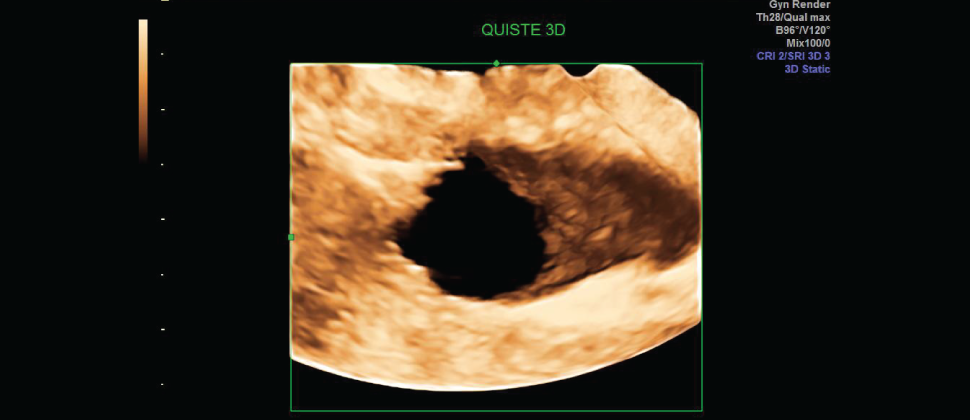

Ecografía Vaginal, este es un examen de diagnóstico, donde se obtienen imágenes de los órganos internos como: útero, trompas de falopio, ovarios, cuello del útero y vagina. En este estudio se puede detectar:

• Quistes y fibromas